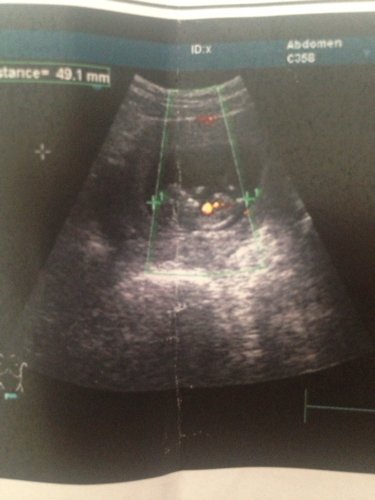

有会看男孩女孩的宝妈吗?帮忙看看、纯属好奇、谢了 点击展开 匿名用户 2014-05-16 16:47 为您推荐: 其他回答 我要看彩超单上的数字比例才能看的出来 匿名用户 2014-05-16 17:10 男的 匿名用户 2014-05-16 17:08 相关问题 宝妈们帮帮忙看看这是男宝还是女宝,男孩女孩都一样就是好奇,谢了…祝大家好孕… 唐氏筛查可以鉴别男孩女孩吗?纯属好奇!懂得帮忙看看 宝宝姓张,想起一个四个字的名字,男孩女孩各一个,谢宝妈